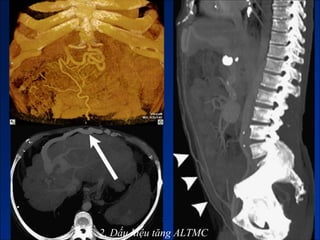

1. Bệnh lý giả xơ gan (Micmic cirrhosis).

1. Bệnh lý giả xơ gan

1. Bệnh lýgiả xơ gan

• #84 Bệnh lý giả xơ gan do - Congenital hepatic fibrosis (phì đại HPT I và thùy bên gan trái, teo gan phải, HPT IV bình thường) - Di căn từ ung thư tuyến vú (phì đại HPT I, bờ gan không đều) - U hạt ở gan (thường phải sinh thiêt). - HC Budd-Chiari (phì đại HPT I, dấu hiệu TALTMC, ).

• #85 Bệnh lý giả xơ gan do - Congenital hepatic fibrosis (phì đại HPT I và thùy bên gan trái, teo gan phải, HPT IV bình thường) - Di căn từ ung thư tuyến vú (phì đại HPT I, bờ gan không đều) - U hạt ở gan (thường phải sinh thiêt). - HC Budd-Chiari (phì đại HPT I, dấu hiệu TALTMC, ).